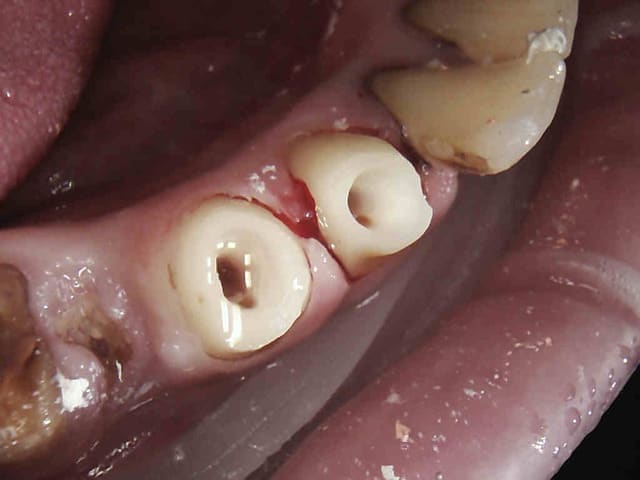

Les 4 en une heure et quart pulpec, taille, empreinte, provisoires. Tarif CMU, rentable ! -)))))

4 zvkifx - Eugenol

5 obhiok - Eugenol

7 ix4kkx - Eugenol

8 kloqft - Eugenol

9 sugvfe - Eugenol

Images jm2g2g - Eugenol